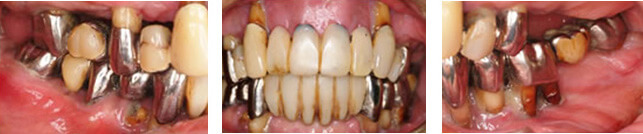

インプラント治療例その2(重度歯周病患者様、上顎に6本下顎に4本インプラント埋入、60歳代女性)

残念ながらここまで歯周病が広範囲かつ重度に進行してしまうと全て抜歯→総義歯が一般的な治療方針となりますが、患者様の強いご希望により必要最小限の本数を用いたインプラント治療によって、固定性補綴物による咀嚼回復が可能となりました。

暫間義歯を装着しCT撮影・診断の後インプラント埋入位置を決定、その位置へ正確に埋入するため作製されたサージカルガイドを用いて手術を行います。

術前

術後